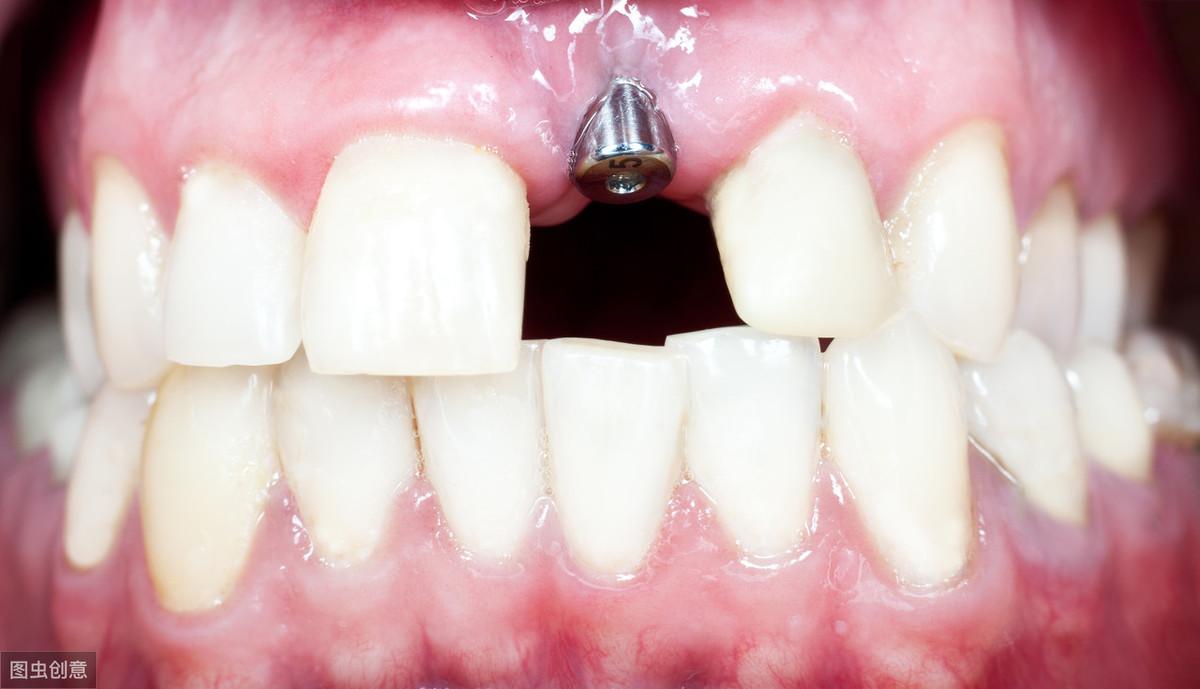

1,種植牙是不是很疼?在患者接受種植手術(shù)之前,會接受種植牙區(qū)域的局部麻醉,所以在手術(shù)過程中患者是不會感受到疼痛的,達(dá)到了手術(shù)的果。

在手術(shù)結(jié)束后的愈合過程中,因為麻醉藥的力已過,患者會有一些不適感或者是疼痛感,但一般來講不是過于激烈的感受,大部分患者是可以忍受的。